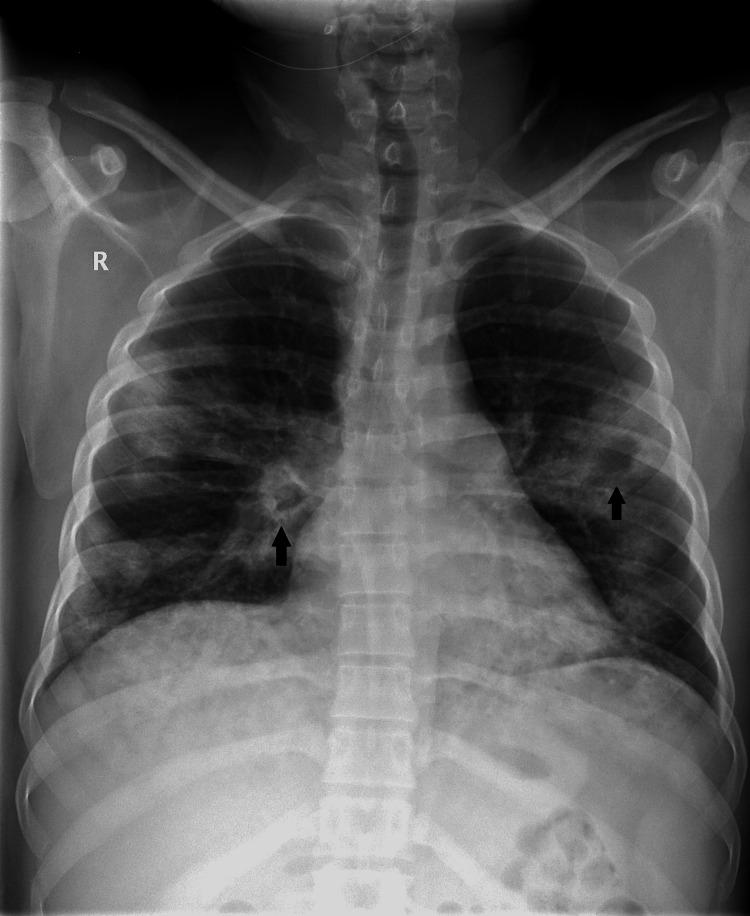

Genetic susceptibility to severe acute respiratory syndrome coronavirus 2 (SARS-CoV-2) morbidity and mortality continues to evolve. This report presents a case of an apparently healthy male adult who developed severe coronavirus disease 2019 (COVID-19) and a study on relevant genetic mutations, namely, angiotensin-converting enzyme 2 (ACE2-rs4646994 I/D) gene, glutathione S-transferase (GST) M1 and T1 gene, and miR-423 rs6505162 C>A gene polymorphism. Results showed that the ACE-DD genotype of ACE2, (GSTM1+/+) (GSTT1-/-) genotype of GST gene, and CA genotype (heterozygosity) of miR-423 rs6505162 genes, which were found in the patient, could be independent risk factors of severe COVID-19, even without comorbidities.

对严重急性呼吸综合征冠状病毒2(SARS-CoV-2)发病和死亡的遗传易感性仍在不断演变。本报告介绍了一例表面健康的成年男性患重症2019冠状病毒病(COVID-19)的病例以及一项关于相关基因突变的研究,即血管紧张素转换酶2(ACE2-rs4646994 I/D)基因、谷胱甘肽S-转移酶(GST)M1和T1基因以及miR-423 rs6505162 C>A基因多态性。结果显示,在该患者中发现的ACE2的ACE-DD基因型、GST基因的(GSTM1+/+)(GSTT1-/-)基因型以及miR-423 rs6505162基因的CA基因型(杂合性),即使在没有合并症的情况下,也可能是重症COVID-19的独立危险因素。